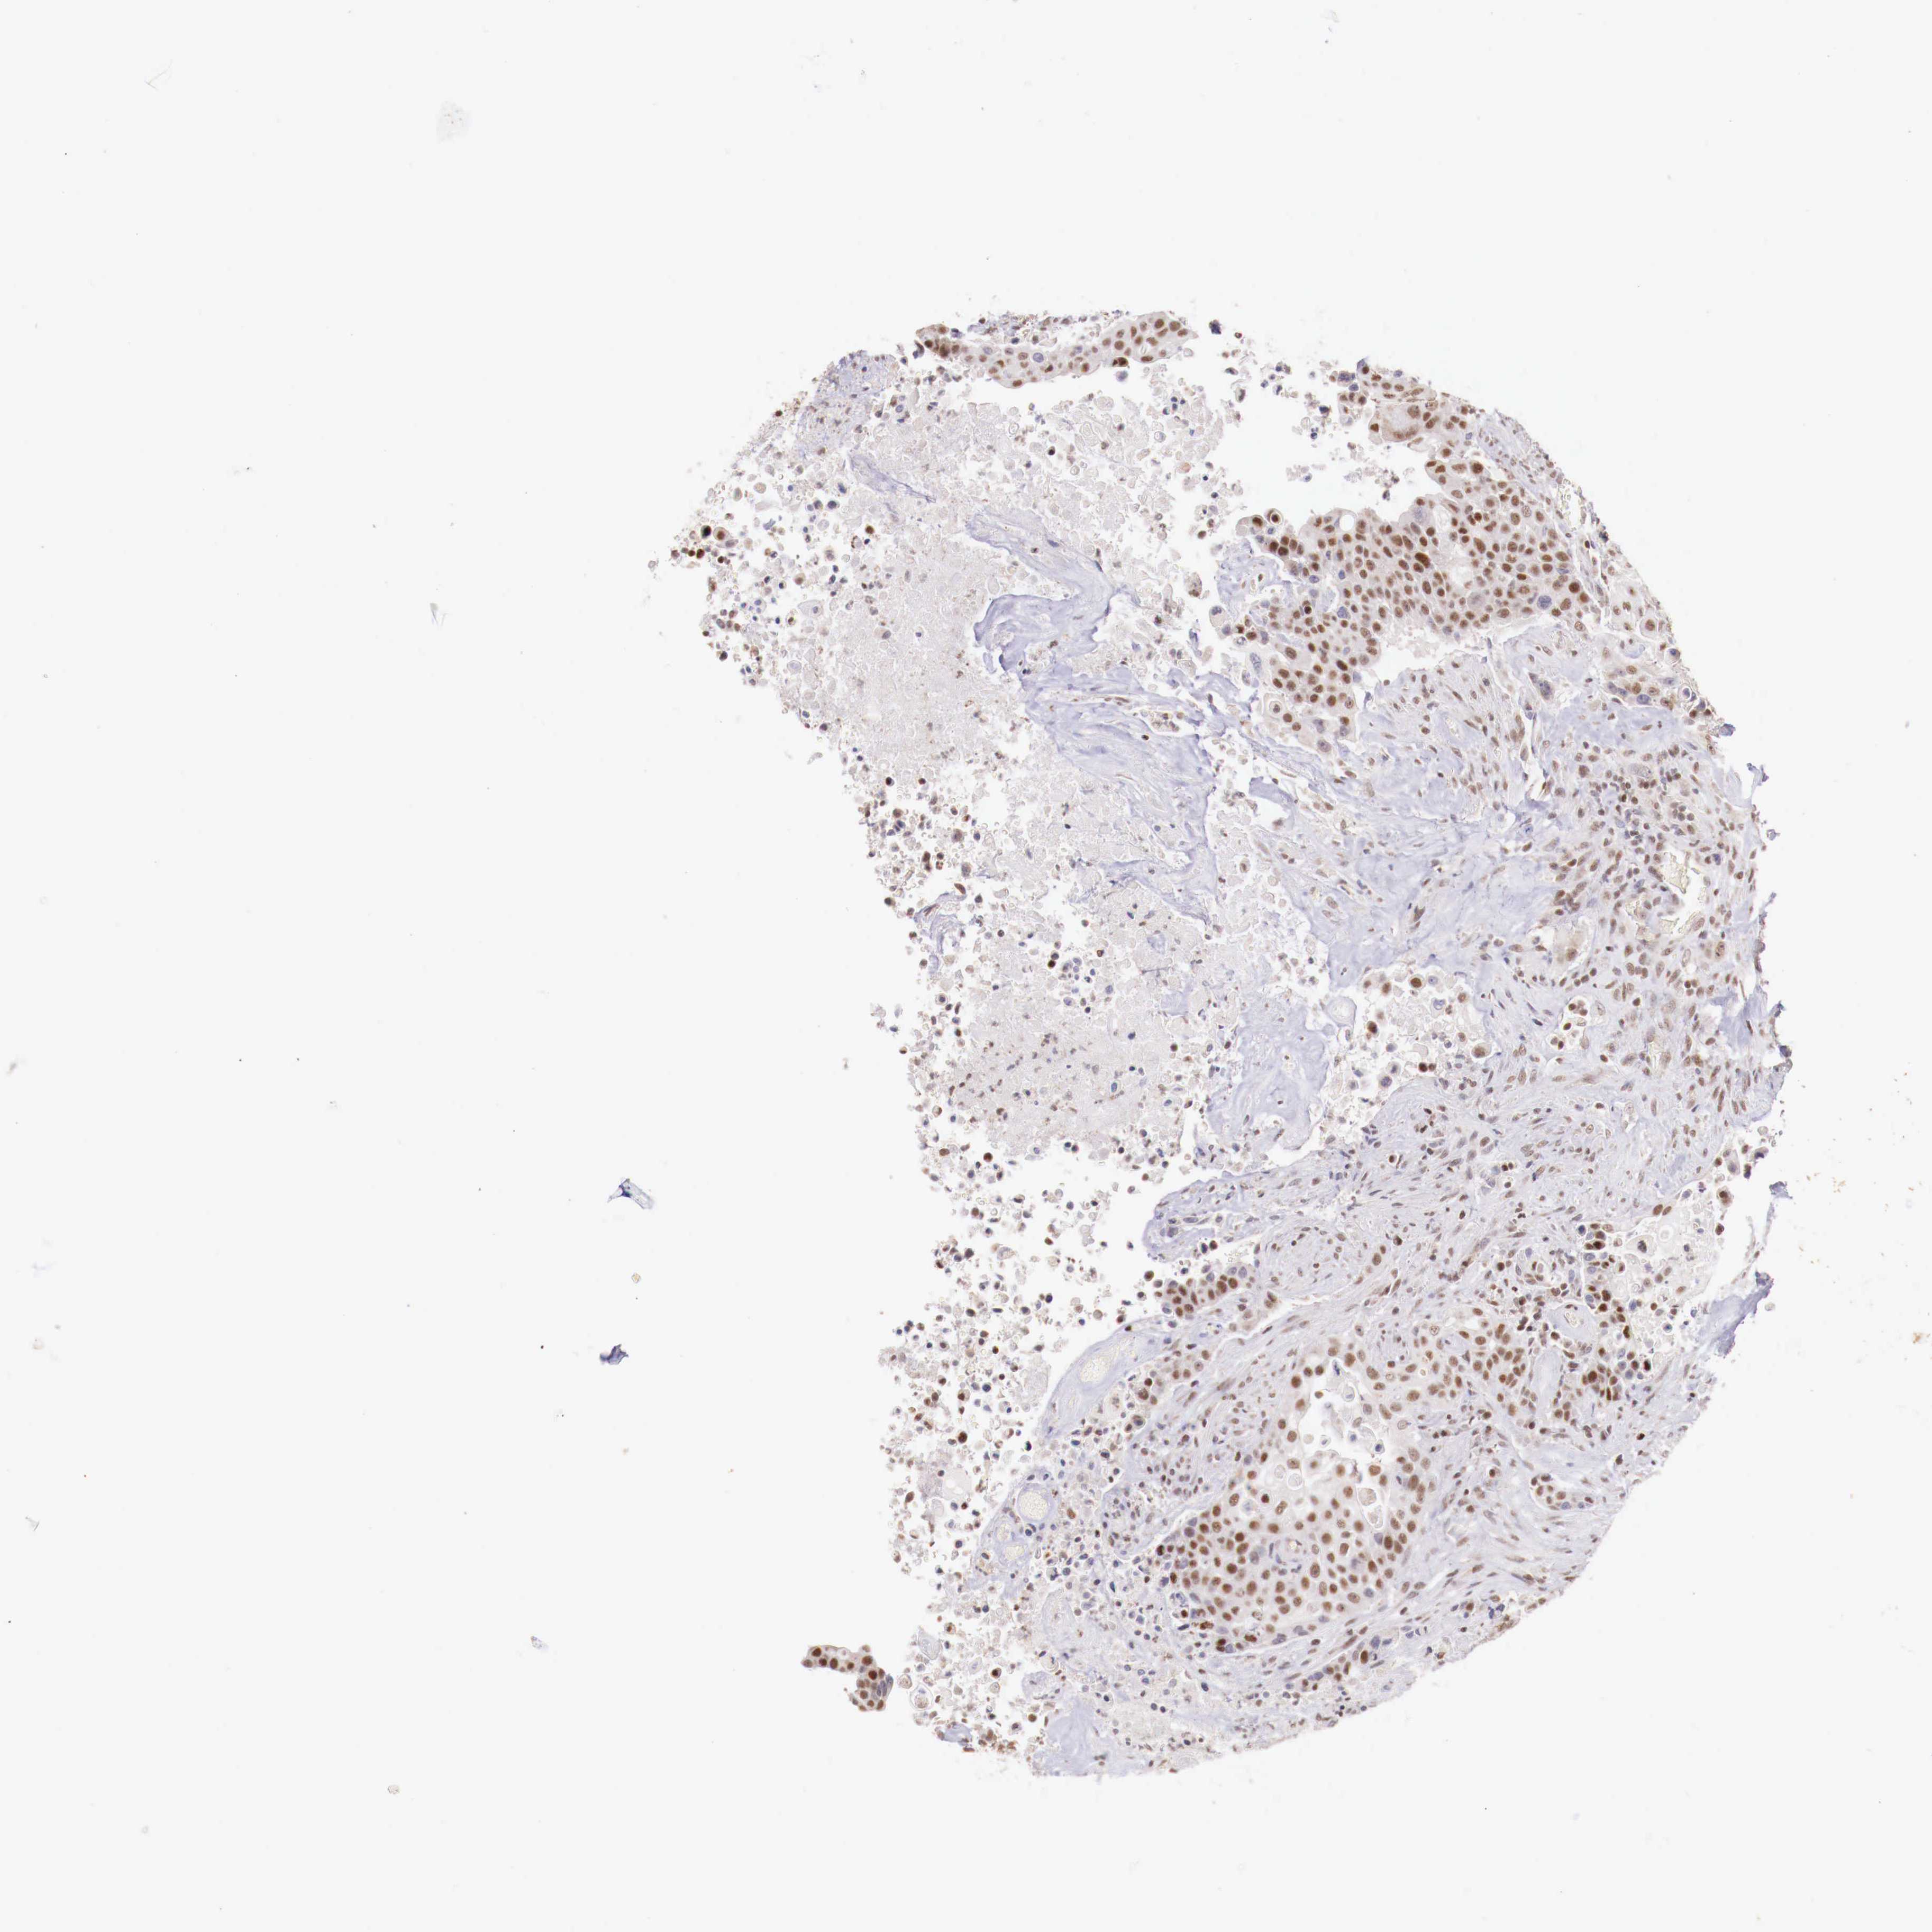

UROTHELIAL CANCER - Protein expressioni

A mouse-over function shows sample information and annotation data. Click on an image to view it in a full screen mode. Samples can be filtered based on level of antibody staining by selecting one or several of the following categories: high, medium, low and not detected. The assay and annotation is described here.

Note that samples used for immunohistochemistry by the Human Protein Atlas do not correspond to samples in the TCGA dataset.

Antibody stainingi

Antibody staining in the annotated cell types in the current human tissue is reported as not detected, low, medium, or high, based on conventional immunohistochemistry profiling in selected tissues. This score is based on the combination of the staining intensity and fraction of stained cells.

Each image is clickable and will lead to virtual microscopy that enables deeper exploration of all samples and also displays staining intensity scores, fraction scores and subcellular localization as well as patient and tissue information for each sample.

Antibody HPA001853

Antibody HPA012292

Antibody CAB000330

Staining

High

Medium

Low

Not detected

Intensity

Strong

Moderate

Weak

Negative

Quantity

>75%

75%-25%

<25%

None

Location

Nuclear

Cytoplasmic/membranous

Cytoplasmic/membranous,nuclear

Urothelial carcinoma, High grade

Urothelial carcinoma, Low grade